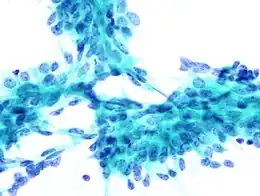

Microphotographie d'un échantillon par ponction à l'aiguille fine de la glande salivaire présentant un carcinome adénoïde kystique

La biopsie à l’aiguille fine (BAF) ou cytoponction, est une méthode de diagnostic consistant à prélever des cellules et du tissu dans des nodules ou du liquide dans des kystes et des ganglions lymphatiques à l'aide d'une aiguille très fine montée sur une seringue pour effectuer ensuite un examen cytologique du prélèvement au microscope. C'est une procédure chirurgicale de diagnostic sûre et non invasive, qui évite souvent les biopsies chirurgicales majeures. Contrairement à la biopsie par forage, la biopsie à l'aiguille fine est généralement indolore et ne provoque que peu de complications (saignement, infection). Elle est le plus souvent employée pour la détection des cancers du sein, de la thyroïde ou des ganglions lymphatiques dans le cou, l'aine ou l'aisselle[1].